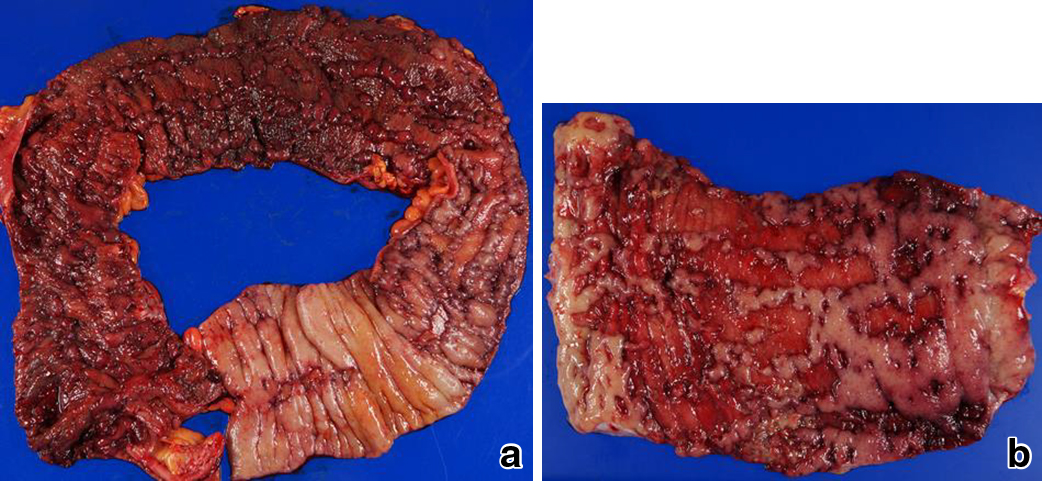

術前経過:潰瘍性大腸炎発症2年後に再燃し,重症の診断で入院した.入院時は排便回数30回/日,顕血便(+),体温37.5°C,脈拍107回/分で,血液生化学検査所見ではHb 14.7 g/dl,CRP 14.6 mg/dl,WBC 15,600/μlであった.ステロイド大量静注療法を施行し,排便回数は16回/日まで減少したが,血便が増加し,Hb 7.1 g/dlと貧血が進行したため,入院16日目,手術の方針とした.肛門管に深い潰瘍を認めたため,結腸亜全摘,S状結腸粘液瘻造設,回腸人工肛門造設術を行った(Fig. 1a).

a, b: Resected specimen showed diffuse ulcers involving the muscle layer. There is scarce mucosa throughout the entire colon and rectum.

術後経過:術後5日目に残存大腸から大量出血を認め,収縮期血圧73 mmHg,Hb 5.4 g/dlと低下したため緊急手術を行った.出血部位の確認を目的とした内視鏡検査は大量出血およびショックのため行わなかった.

第2回目手術:粘液瘻の離開を合併し腹腔内に大量の膿汁の貯留があり,高度の癒着と腹腔内感染を認めたため再建は行わず,直腸部分切除,Hartmann手術を行った.次回再建時に直腸を安全に同定することを目的とし,直腸は腹膜翻転部口側1 cmで縫合閉鎖した(Fig. 1b).